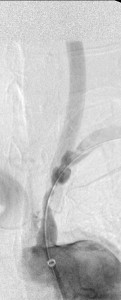

The 4 images you see above were recorded by me during primary stenting of irregular atherosclerotic stenosis of the left subclavian artery in a 54-year-old hispanic female who was referred to my interventional radiology clinic for management of the stenosis. She had presented to her primary care physician with symptoms of hindbrain ischemia upon using her left upper limb and earlier workup confirmed left subclavian arterial stenosis. The 2 top images illustrate the character and severity of her disease, the first image in the bottom row shows the process of balloon-expandable stenting of the disease, while the 2nd image in the bottom row reveals complete elimination of the stenosis and reappearance of the left vertebral and internal mammary arteires, which were invisible on the pre-intervention angiograms reflecting the severity of the stenosis.